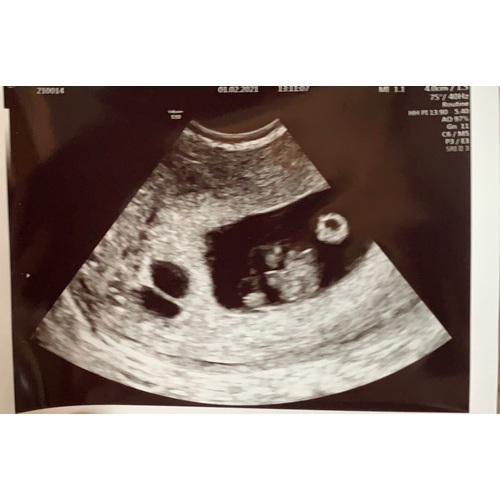

Nou.. ik kan het je vertellen want wij weten nu sinds een week dat we een tweeling krijgen ♥️♥️

Ten eerste had ik echt een mega knaltest terwijl ik 1 dag overtijd was. 2 mega dikke rode strepen!

Ten tweede ben ik me toch een partij gigantisch misselijk geweest!! Niet normaal! Gelukkig zonder overgeven maar pffff.. heb nu “emasafene” en das een geschenk uit de hemel!

Ten derde.. ben ik moe en wil ik alleen maar slapen... terwijl ik in lockdown zit met mn werk en geen flikker doe (bijna) ben ik toxh moe moe moe

En mn buik! Je kunt echt al zien dat ik zwanger ben terwijl ik nu 9 weken ben

Ik was eerst in shock toen ik het hoorde maar nu het geland is denk ik: wauwwww wat een wonder! ♥️♥️

Ik ben morgen ook 9 weken zwanger van een tweeling. Ik ben voor het eerst zwanger dus kan ook geen vergelijking maken.. Maar heb niet het gevoel dat mijn klachten heel extreem zijn.

Herken wel de klachten die hier al benoemd werden. Veel honger (ook snachts wakker worden van de honger) en erg moe. Verder wel een stuk grotere, maar niet perse pijnlijke borsten. En sinds een aantal dagen last van mijn onderrug/stuitje?